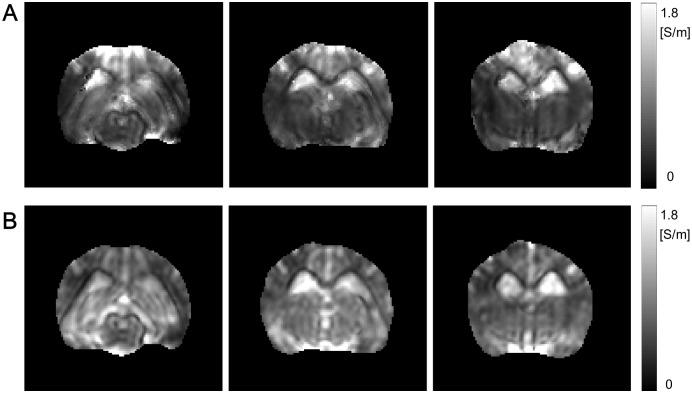

Transcranial direct current stimulation (tDCS) is a widely used non-invasive brain stimulation technique by applying low-frequency weak direct current via electrodes attached on the head. The tDCS using a fixed current between 1 and 2 mA has relied on computational modelings to achieve optimal stimulation effects. Recently, by measuring the tDCS current induced magnetic field using an MRI scanner, the internal current pathway has been successfully recovered. However, up to now, there is no technique to visualize electrical properties including the electrical anisotropic conductivity, effective extracellular ion-concentration, and electric field using only the tDCS current in-vivo. By measuring the apparent diffusion coefficient (ADC) and the magnetic flux density induced by the tDCS, we propose a method to visualize the electrical properties. We reconstruct the scale parameter, which connects the anisotropic conductivity tensor to the diffusion tensor of water molecules, by introducing a repetitive scheme called the diffusion tensor J-substitution algorithm using the recovered current density and the measured ADCs. We investigate the proposed method to explain why the iterative scheme converges to the internal conductivity. We verified the proposed method with an anesthetized canine brain to visualize electrical properties including the electrical properties by tDCS current.

经颅直流电刺激(tDCS)是一种广泛应用的非侵入性脑刺激技术,通过在头部贴附电极施加低频弱直流电来实现。使用 1 到 2 mA 固定电流的 tDCS 依赖于计算模型来实现最佳的刺激效果。最近,通过使用 MRI 扫描仪测量 tDCS 电流感应磁场,已经成功恢复了内部电流通路。然而,到目前为止,还没有技术可以仅使用体内 tDCS 电流可视化包括各向异性电导率、有效细胞外离子浓度和电场在内的电特性。通过测量 tDCS 诱导的表观扩散系数(ADC)和磁通密度,我们提出了一种可视化电特性的方法。我们通过引入一种称为扩散张量 J 替代算法的重复方案,利用恢复的电流密度和测量的 ADC 值来重建连接各向异性电导率张量和水分子扩散张量的比例参数。我们研究了该方法,以解释为什么迭代方案可以收敛到内部电导率。我们使用麻醉犬脑验证了该方法,以可视化包括 tDCS 电流在内的电特性。